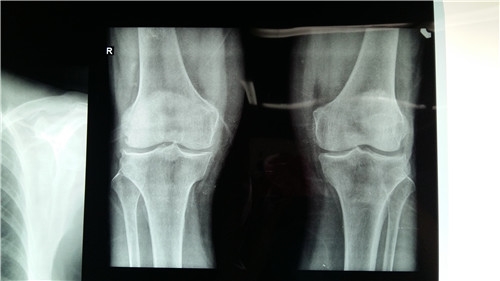

关节科